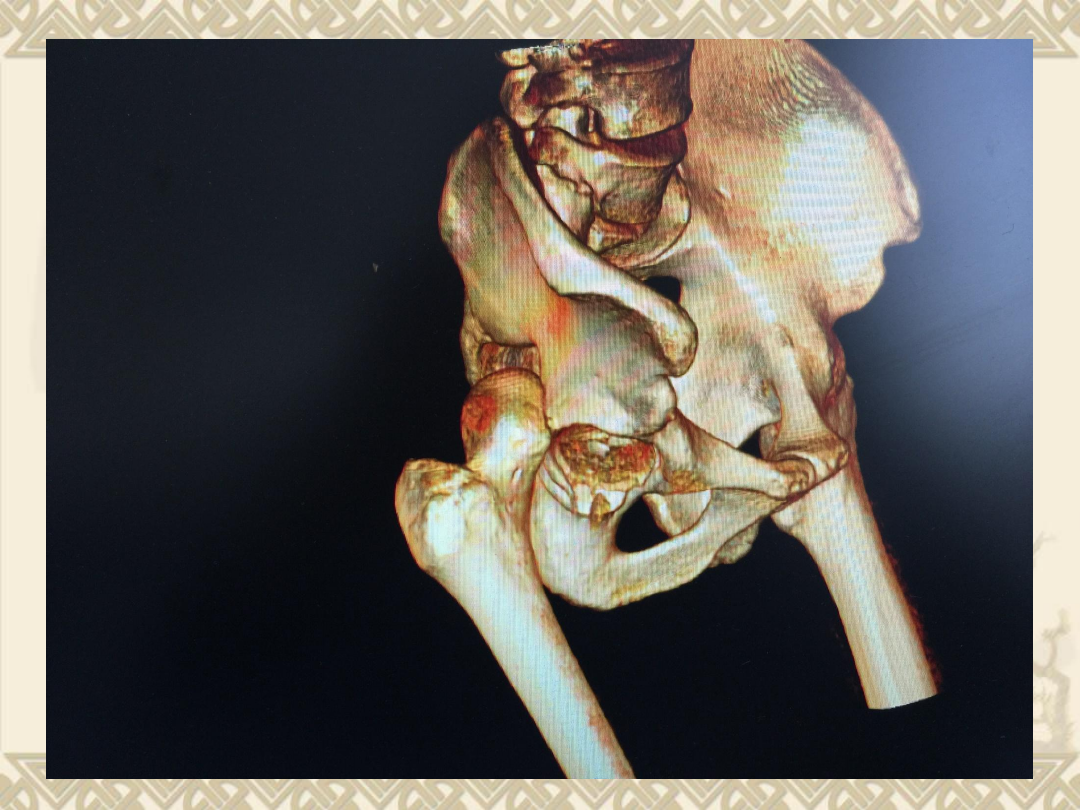

CT

v

1

、右股骨头骨折(

Pipkin

Ⅳ型骨折)

2

、髋关节后脱位

3

、髋臼后缘骨折